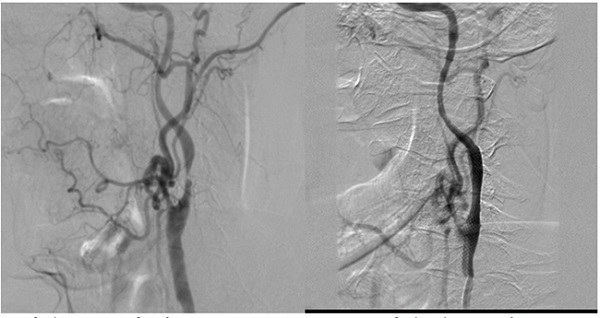

Trường hợp 1:

Bệnh nhân nam, 71 tuổi, hẹp động mạch cảnh trong trái, chóng mặt say sẩm, yếu 1/2 phải.

1a: trước đặt stent.                            Hình 1b: sau đặt stent

Sau can thiệp nong và đặt stent, các triệu chứng bệnh nhân cải thiện, bớt chóng mặt, tay chân phải mạnh hơn, đi lại bình thường.